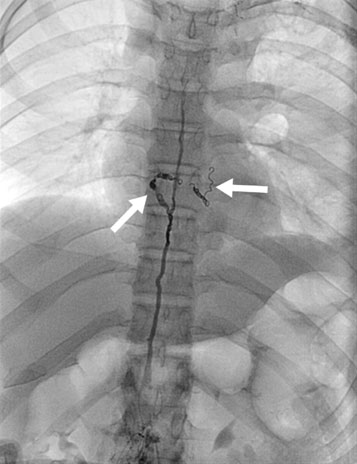

Diagnostic Imaging

Lymphangiography: An X-ray examination of the lymphatic vessels and nodes after injection of a contrast medium (dye). Useful for staging lymphomas.